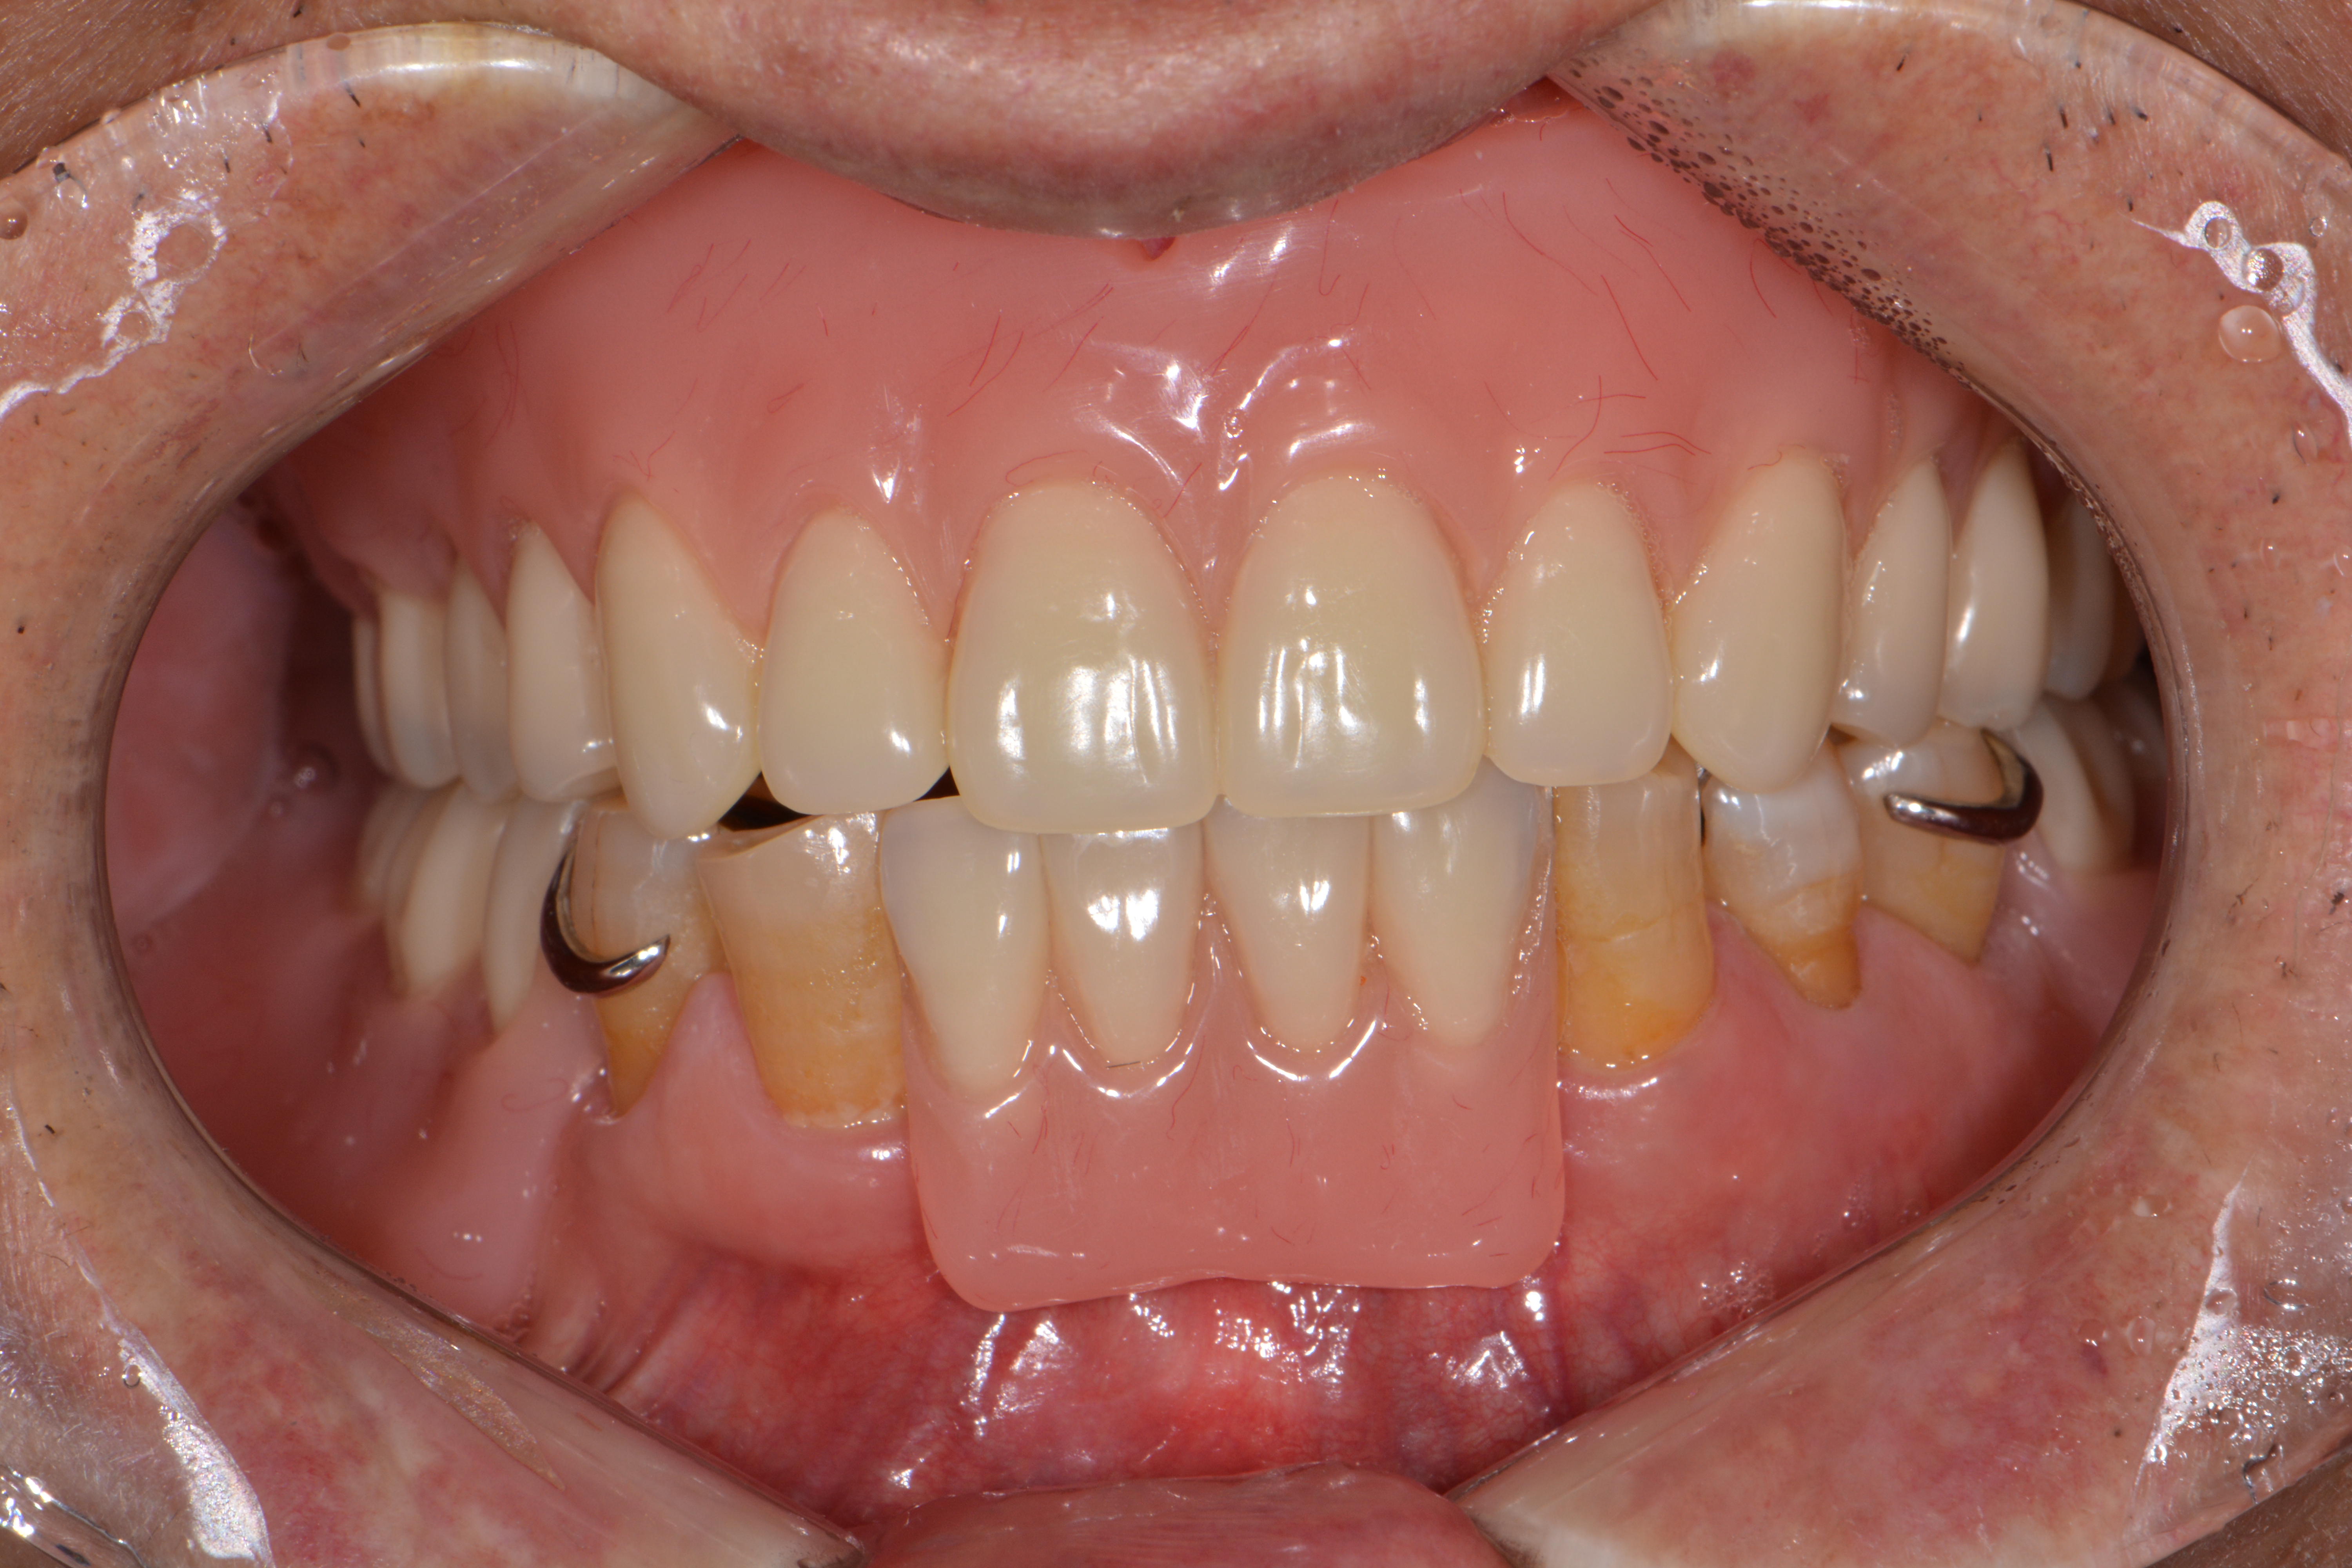

상악 완전틀니, 하악 부분틀니

Before

After

아래 쪽에 간혹 튼튼한 치아가 몇개 남아있을 때가 있습니다.

이런 치아는 발치하지 않고 부분틀니를 지지해주는 치아로 활용하게 되면

저작 만족도를 높일 수 있습니다.